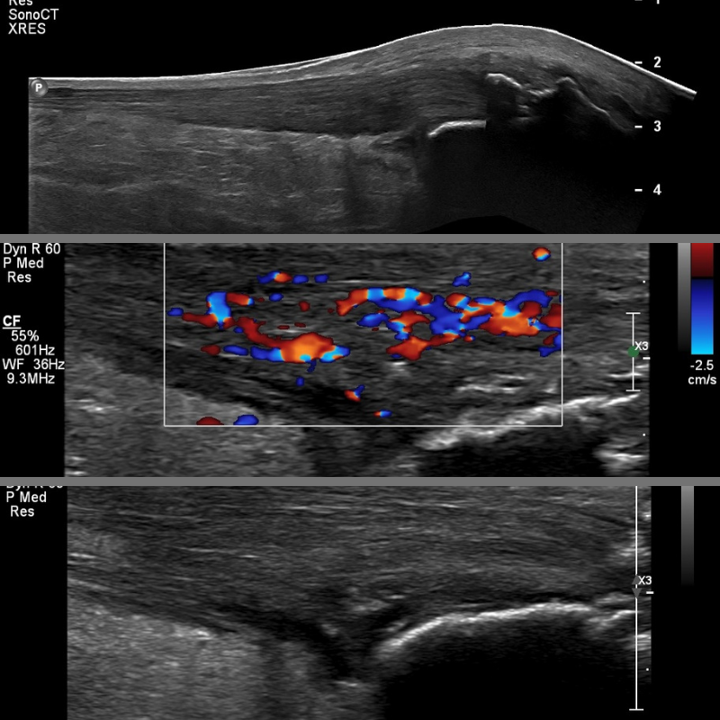

Ultrasound can very clearly show the difference between a normal Achilles tendon (Right top) and one that has tendinopathy (Right Middle) as the tendinopathic tendon is often significantly thicker than a normal Achilles tendon.

In addition to that a tendinopathic tendon tends to be hypoechoic. What that means is that the tendon is less bright on ultrasound. If the tendon has more fluid in it i.e. is more swollen than automatically it appears darker on ultrasound.

Ultrasound can use power Doppler which shows blood flow. A normal Achilles tendon has no obvious blood flow is seen. In tendinopathic Achilles tendon is oftentimes there is marked vascularity (right bottom) seen which again can be helpful for diagnosis. Because ultrasound is dynamic it can also demonstrate any potential serious structural defects in the tendon.

Another option is ultrasound guided injections for Achilles tendinopathy. In the Sonoscope clinic, we perform ultrasound guided hydrodistension injections, which inject a large volume of saline (salty water) water into the interface between the Achilles tendon and the fat pad that lies in front of the Achilles tendon. This “stripping “procedure disrupts the increased activity of blood vessels in the painful tendon, which reduces pain by disrupting this unhelpful increased blood circulation which leads to increased levels of pain. Although more recent studies have not found evidence for this mechanical effect of reducing neovascularity.